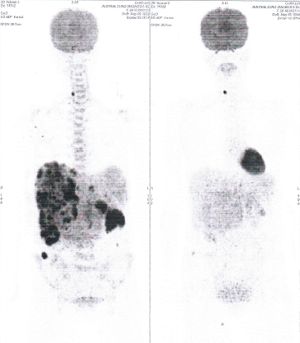

CASE NO: 4 (PROSTATE CANCER)

A middle-aged man with castration resistant prostate cancer and massive bone metastases, failed all currently available cancer treatment, including with the new and expensive drug XTANDI. After a few treatment, most of the bone metastases went into remission, and the remaining ones are less active. Treatment will continue. Cases no: 3 and 4 show that terminal prostate cancer today can be cured with our new cancer treatment.

CASE NO: 5 (BREAST CANCER)

A middle-aged woman with breast cancer that has spread to the anterior chest wall, and numerous chemotherapy could not stop the spread of cancer. After a few treatment, almost all the cancer went into remission. About 6 months later, she is still in remission.

CASE NO: 6 (BREAST CANCER)

A middle-aged women treated for breast cancer now presents with massive liver metastases and a few bone metastases. She refused conventional chemotherapy and came to see us. After just 2 treatment, most of the cancer went into remission and those remaining are less active. Treatment will continue until complete remission.